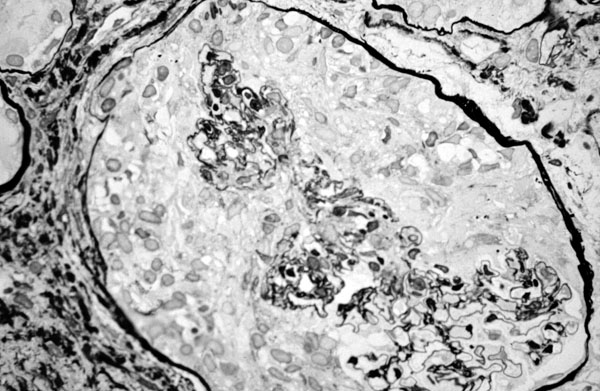

Wegener granulomatosis, glomerulus, Jones silver stain

ANCA positive crescentic glomerulonephritis - micro, silver stain for basement membrane - the crescent and collapsed capillary tuft are better visualized.